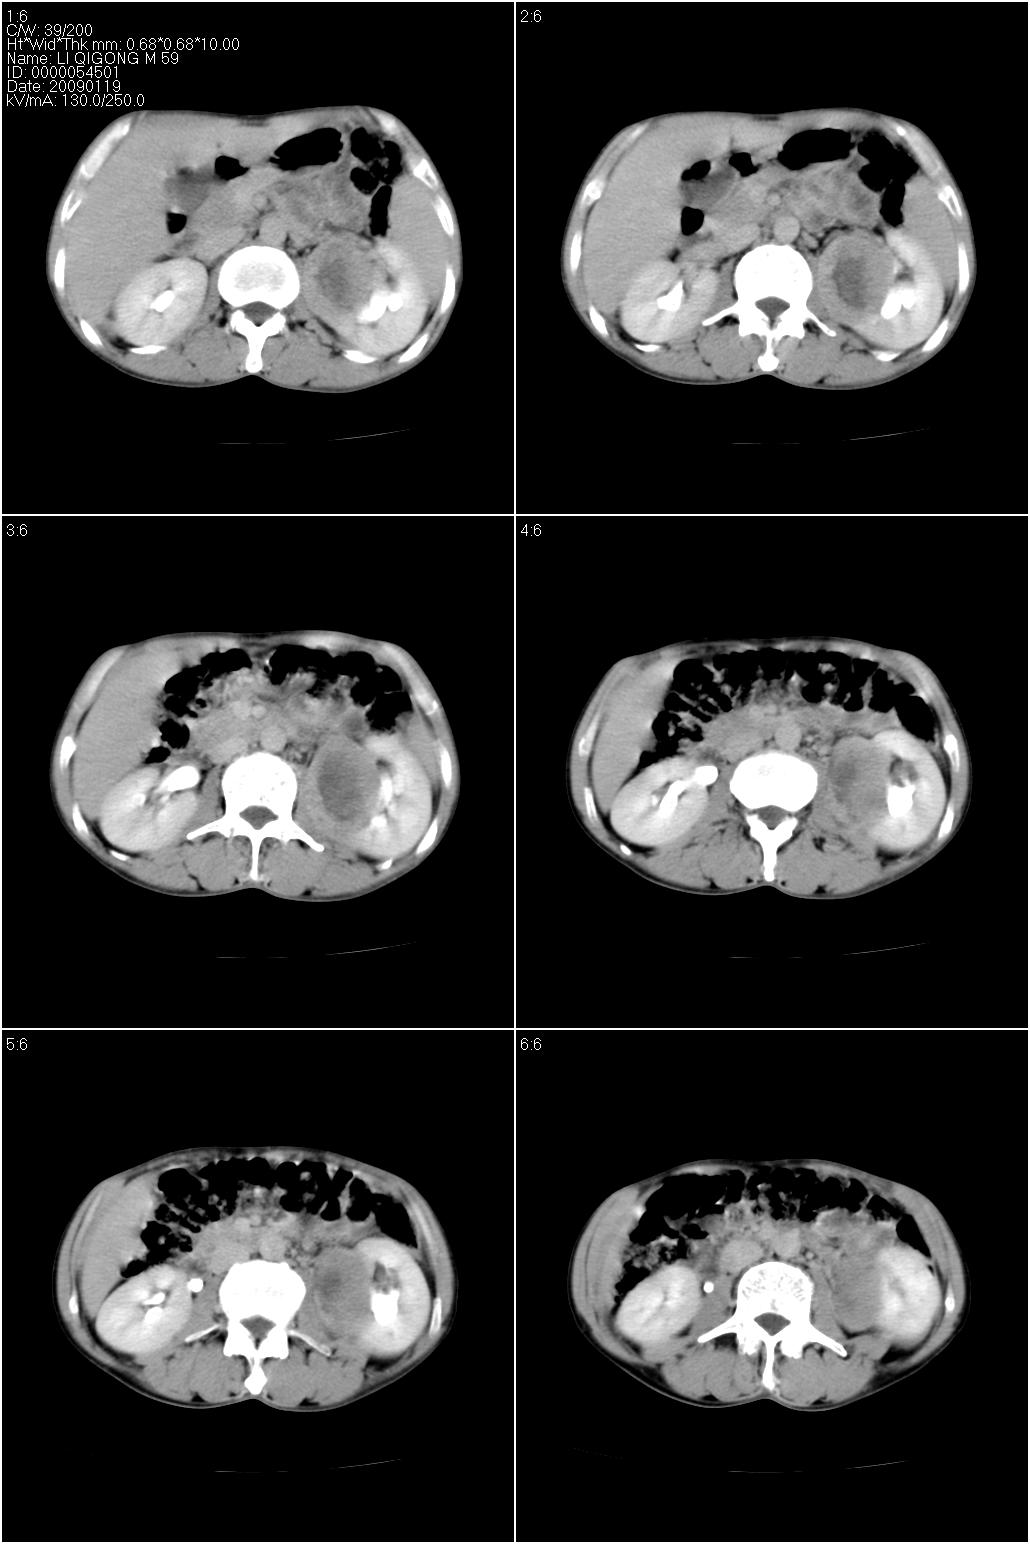

标题: CT17771:男性,59岁。体检发现左肾占位。

男性,59岁。体检发现左肾占位。自诉无尿血、尿痛。

无痛无血尿,左肾实质占位,有明显强化,中心坏死不规则,应该肾癌无疑。

应该考虑左肾癌并肾盂积水

2、左肾占位,呈不均匀性强化,中央有无强化的坏死区。

3、左肾门旁有侧枝开放,提示左肾静脉癌栓形成可能。

支持 考虑左肾癌并肾积水。

考虑左肾癌并肾盂积水。

考虑左肾癌并肾积水。